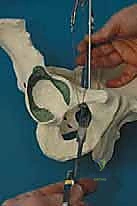

2. سلسلة قطع العظام (The 5 Osteotomies)

يكمن سر نجاح جراحة PAO في إجراء خمسة قطوع عظمية منفصلة حول الحُق، لتحريره بالكامل عن باقي الحوض، مع ترك العمود الخلفي سليماً كدعامة أساسية.

القطع الأول: القطع الإسكي غير المكتمل (Incomplete Ischial Osteotomy)

باستخدام إزميل خاص ذو زاوية (Angled Osteotome)، يتم إجراء قطع في عظم الإسك أسفل الحُق مباشرة (في الأخدود تحت الحُقي). يتم هذا القطع بتوجيه الأشعة السينية (Fluoroscopy) لضمان عدم اختراق المفصل. يحرص الدكتور هطيف على إبعاد العصب الوركي والأوعية السدادية بأمان تام.